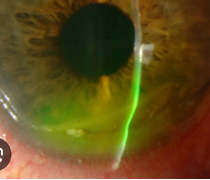

Objective: not at limbus (thin line of clear cornea), begins at 3/9 oclock, swiss cheese appearance

Band Keratopathy: calcium deposits forming a band-like appearance across the cornea (bowmans). May cause vision impairment or irritation.

Causes: Chronic uveitis, JIA, interstitial keratitis, corneal edema, phithsis bulbi, glaucoma, retinal surgery, renal failure

Plan:

Mild: Lubricants

Moderate: EDTA 3% chelation with cotton swab. Put on 10-60 minutes, saline rinse.

If epi defect: Antibiotic drop QID and ointment (if epi defect), cyclo 1%, BCL.

Severe: Consider PTK